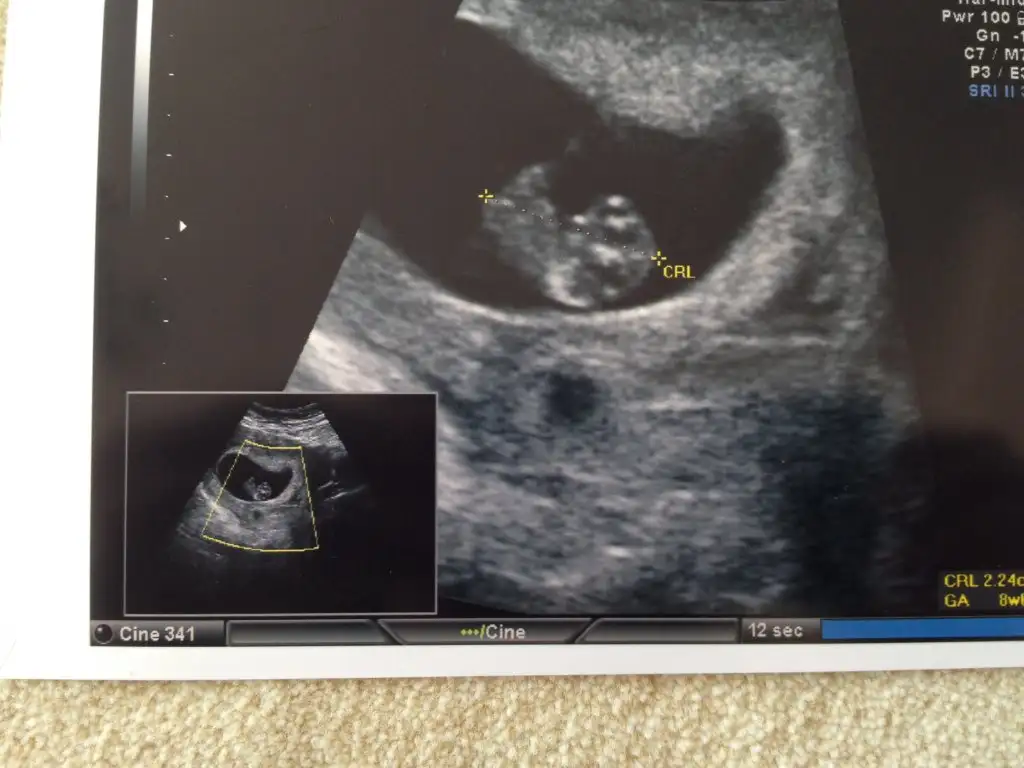

Eki Görüntüle 1628656 Burdada 6+3 sanırm